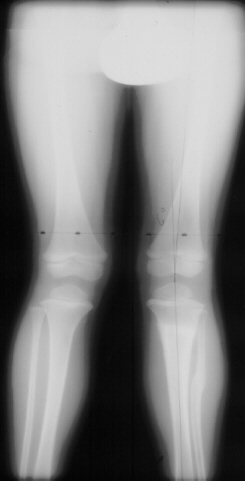

The history of this lesion is for rapid recovery of the valgus if significant growth is remaining. This child had an osteotomy, 3 Months post Surgery the mechanical axis on the left was 6 degrees. The x-ray at 9 months post surgery showed the mechanical axis on the left was 10 degrees.